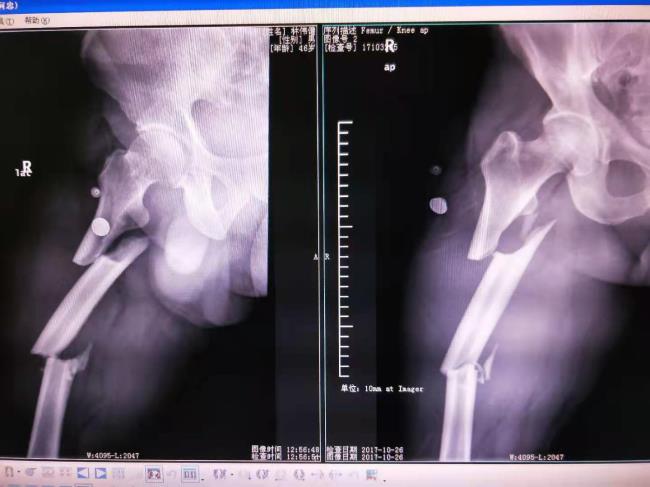

病例1、右股骨多段粉碎性骨折治前及治疗后X线片